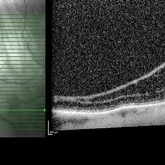

Diabetic Macular Edema

Optical coherence tomography of an 54-year-old female with diabetic macular edema affecting both eyes. Patient has a history of proliferative diabetic retinopathy s/p PRP/PPV/MP/EL, and glaucoma s/p tube shunt in both eyes. There has been a persistence of her macular edema and limited response to antiVEGF therapy, which puts into question whether there is another cause for her edema. Leading the possible causes is her renal insufficiency and fluid retention. Patient was seeing 20/50 in the right eye and 20/80 in the left eye.

Photographer: Olivia Rainey

Imaging device: Heidelberg Spectralis

Condition/keywords: anti-VEGF, diabetic macular edema, edema, glaucoma, optical coherence tomography (OCT), pan-retinal photocoagulation (PRP), proliferative diabetic retinopathy (PDR)